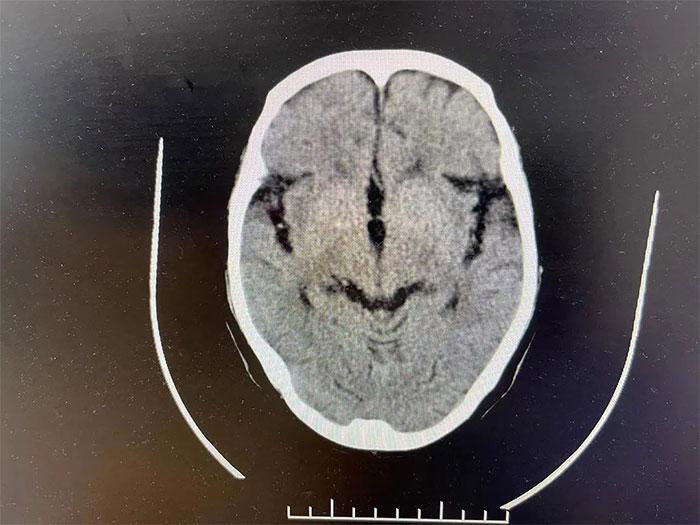

▲ 通過治療,出血已基本吸收